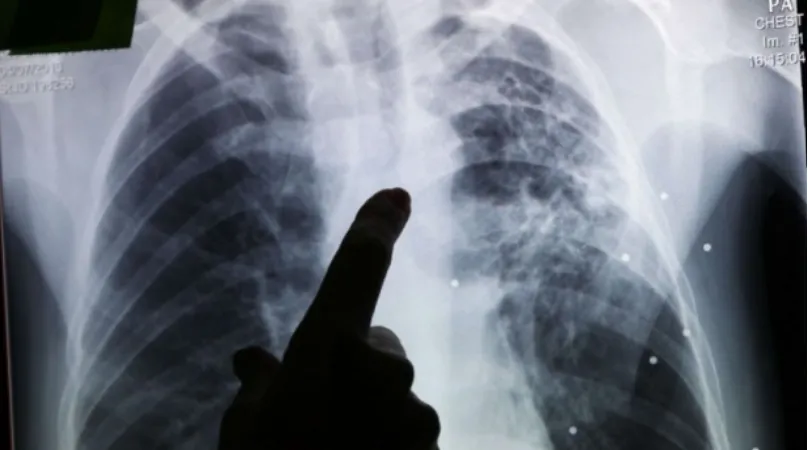

The Moroccan Ministry of Health and Social Protection has released alarming statistics indicating that more than 53% of new tuberculosis cases reported in 2025 are extrapulmonary forms of the disease. This significant finding highlights an urgent need for enhanced awareness and early detection efforts across the nation. In a statement released to coincide with World Tuberculosis Day 2026, celebrated under the theme "Tuberculosis Beyond the Lungs: Let's Raise Awareness of Extrapulmonary Forms," the Ministry emphasized the necessity of increasing clinical vigilance among healthcare professionals to ensure timely diagnosis and appropriate care for affected individuals.